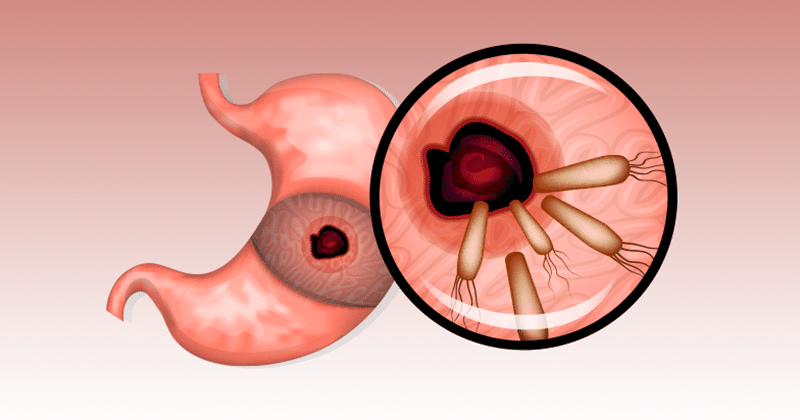

הליקובקטר פילורי (Helicobacter Pylori) - אולי לא שמעתם על הבקטריה הזו. הליקובקטר פילורי הוא יצור קטנטן שחי במעיים שלנו ומציק לשני שליש מאוכלוסיות העולם והוא למעשה, אחד מהגורמים העיקריים להמון בעיות בריאות אצל מליארדי אנשים.

על פי מומחים, מאוד קשה לאבחן את ה- הליקובקטר פילורי בלי בדיקות לגיטימיות. המיקרואורגניזם הם מה שאתם קוראים לו ובצדק, יצור חי ודביק, עם תסמינים בעייתיים שחי במעיים.

אולי אתם מעדיפים לא לדעת עובדה זו, אבל עובדה היא שהחיידק המסוים הזה שחי בתוך המעיים שלנו יכול לחמוק אל תוך הגוף שלנו ולגרום לנזק.